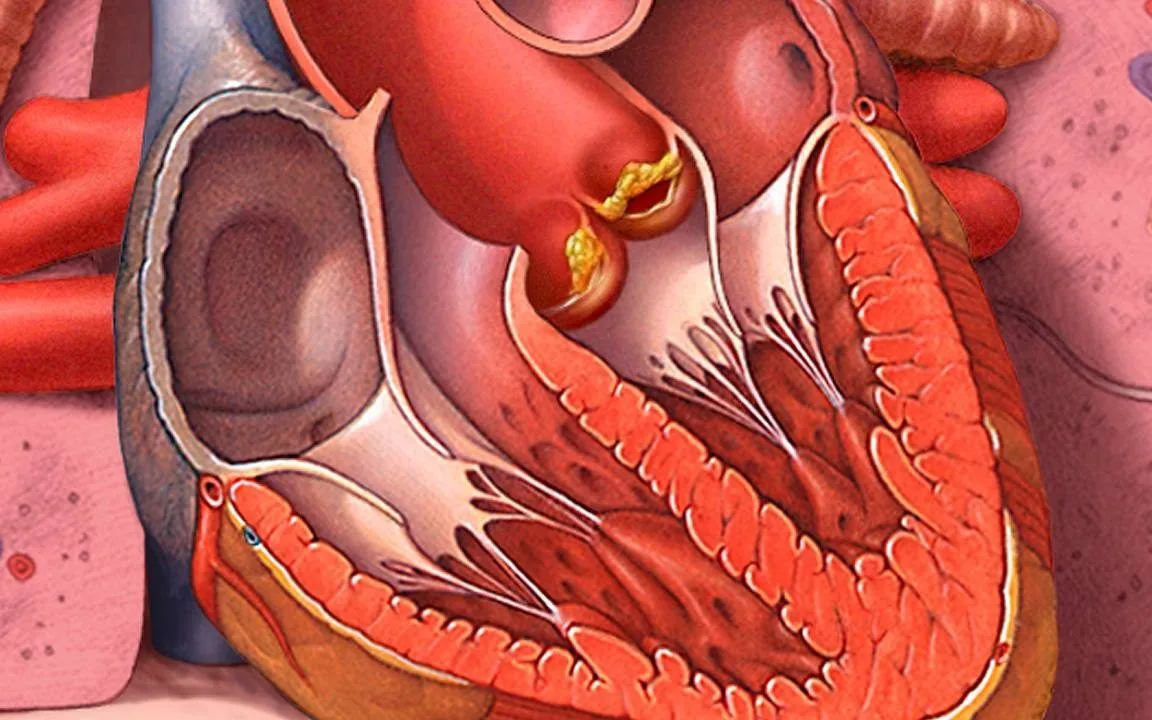

التهاب شغاف القلب الحاد (Acute Endocarditis) هو حالة تتميز بالتهاب الغشاء الداخلي للقلب، المعروف أيضًا باسم الشغاف القلبي. يحدث التهاب شغاف القلب الحاد عادةً نتيجة للعدوى البكتيرية التي تصل إلى الغشاء الداخلي للقلب.

6. تغيرات في صمامات القلب: يمكن أن يؤدي التهاب الشغاف إلى تلف في صمامات القلب مما يسبب تشوهات في وظيفة القلب.